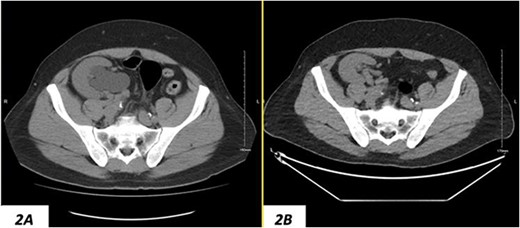

Despite a new onset proteinuria of 50 mg/dl, he continued to have a good functioning graft with a creatinine level of 93 μmol/l corresponding to an estimated glomerular filtration rate (eGFR) of 78 ml/min/1.73 m2. Nonetheless, he had also been noting an inguinal bugle that becomes more prominent as the day progressed, and it regressed at night. Upon further investigations, an ultrasound of the allograft revealed moderate-to-severe hydronephrosis. Further imaging using computed tomography scan (CT) confirmed the presence of upstream moderate hydronephrosis (Figs 1A and2A) along with a reported herniation of the ureter in a right inguinal hernia, resulting in a focal distal ureteric dilatation of 3.5 cm (Fig. 3A).

(A) Hydronephrosis of the allograft ureter on preoperative coronal CT scan; (B) significant improvement of hydronephrosis on the 10-month postoperative image.